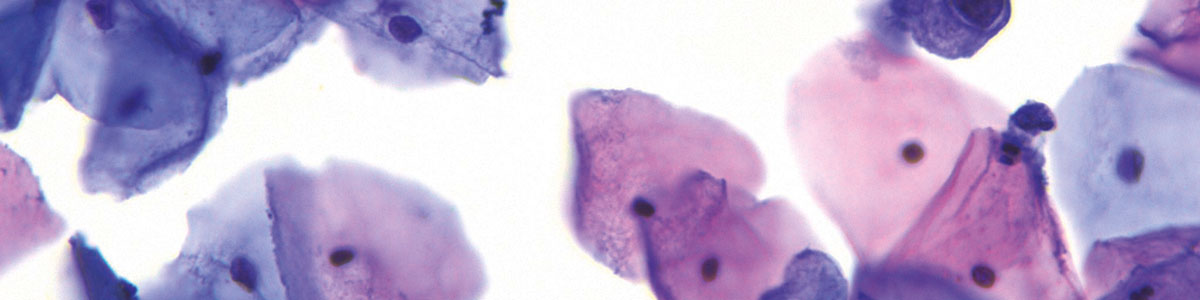

Mit Präzision und Sorgfalt analysieren wir Ihre eingesendeten zytologischen Präparate, um frühzeitig Krankheiten zu erkennen und die Gesundheit unserer Patienten zu schützen. Unsere hochqualifizierten Fachkräfte und modernste Technologie ermöglichen es uns, genaue und zuverlässige Ergebnisse zu liefern. Vertrauen Sie auf unsere Expertise und lassen Sie uns gemeinsam für die Gesundheit unserer Patientinnen sorgen.

Mit Präzision und Sorgfalt analysieren wir Ihre eingesendeten zytologischen Präparate, um frühzeitig Krankheiten zu erkennen und die Gesundheit Ihrer Patientinnen zu schützen.

Unsere qualifizierten Fachkräfte und moderne Analyseverfahren ermöglichen es uns, genaue und zuverlässige Ergebnisse zu liefern.

Wir Ärztinnen und Ärzte der ZytoLabore regional sind Fachärzt:innen für Gynäkologie und Geburtshilfe und als solche seit Jahren spezialisiert auf die gynäkologische Exfoliativzytologie. Und wir sind überzeugt: Gute zytologische Diagnostik setzt gute Kenntnisse in der Klinik voraus. Wir befunden die Abstriche unter Berücksichtigung der Anamnese und lassen unser gynäkologisches Fachwissen in die Beurteilung der Präparate einfließen. So gelingt es uns, das zytologische Know-how unter Einbeziehung der individuellen Klinik der Patientin in einen Befund zu fassen, der unseren Patientinnen optimale Sicherheit bietet, ohne dass die Algorithmen der neuen oKFE-RL mit der notwendigen Individualität ärztlichen Handelns kollidieren. Hohe Qualität unserer Arbeit ist dabei unser ständiges und wichtigstes Ziel. Aus diesem Grund wird das gesamte befundende Personal regelmäßig geschult und neben der Teilnahme an Fortbildungsveranstaltungen in wöchentlichen internen, interdisziplinären Falldemonstrationen für die Erkennung der Pathologie sensibilisiert. Über die vielen angegliederten Dysplasiesprechstunden haben wir ein hohes Aufkommen an auffälligen Präparaten, was die Routine im Umgang mit Pathologien fördert.